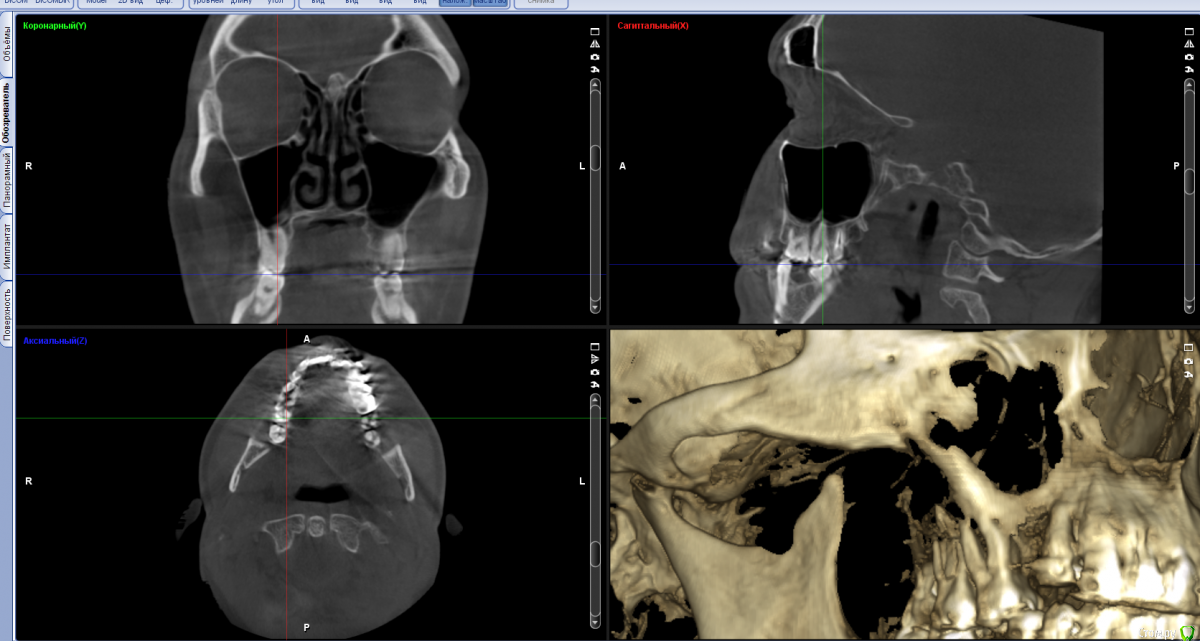

alex889 Опубликовано 8 февраля, 2020 Поделиться Опубликовано 8 февраля, 2020 Подскажите, над предпоследним зубом сверху это инородное тело в гайморовой пазухе? Это могло попасть при лечении каналов зуба мудрости? Может ли такое инородное тело вызывать боли и воспаление в челюстно-лицевой области?Файл КТ: http://fayloobmennik.cloud/7384939 Ссылка на комментарий

wladdX Опубликовано 10 февраля, 2020 Поделиться Опубликовано 10 февраля, 2020 (изменено) Инородных тел не нашёл. То что Вы приняли за инородное тело - перегородка в пазухе Изменено 10 февраля, 2020 пользователем wladdX 1 Ссылка на комментарий